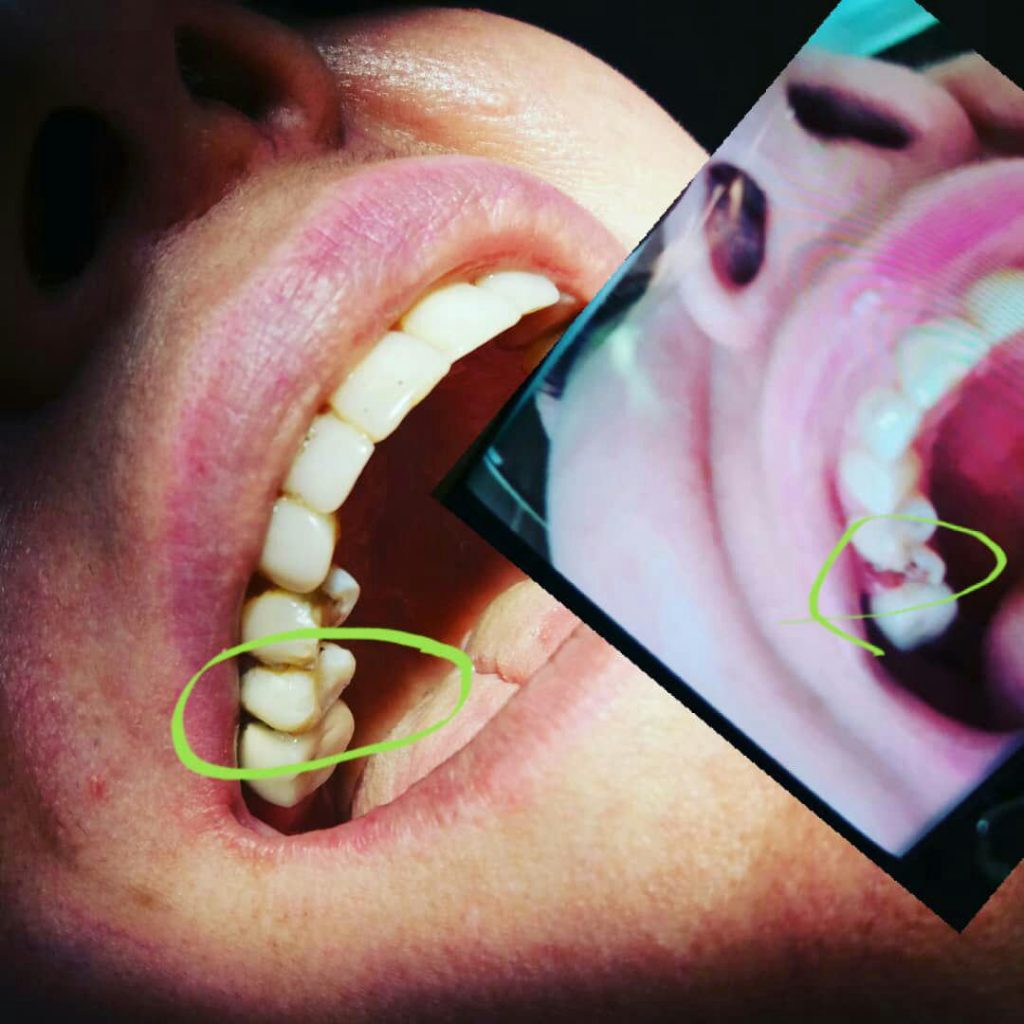

چگونه بهترین گزینه ترمیمی را برای درمان دندانهای آسیبدیده انتخاب کنیم؟

این مهم به بهترین شکل توسط یک دندانپزشک مجرب و خوب مشخص میشود. دندانپزشک با بررسی دندانها و موقعیتی که دارند و همچنین وضعیت دندانهای سالم باقیمانده بهترین شیوه درمانی را توصیه خواهند کرد.